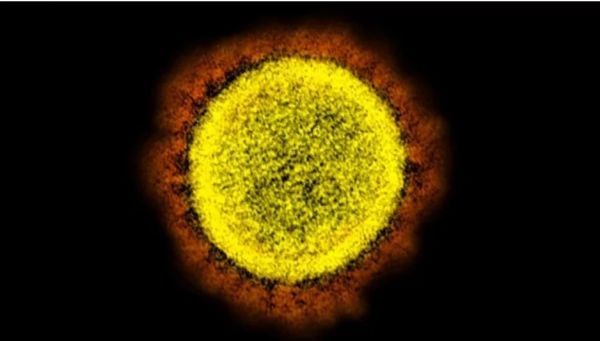

Δραματική προειδοποίηση ΠΟΥ: Η πανδημία απέχει πολύ από το τέλος

Η πορεία της πανδημίας του κοροναϊού αναπτύσσεται με ταχύ ρυθμό, εκθετικά, με αύξηση 9% των κρουσμάτων την περασμένη εβδομάδα, έβδομη συνεχόμενη εβδομάδα αυξητικής τάσης και με 5% αύξηση των θανάτων